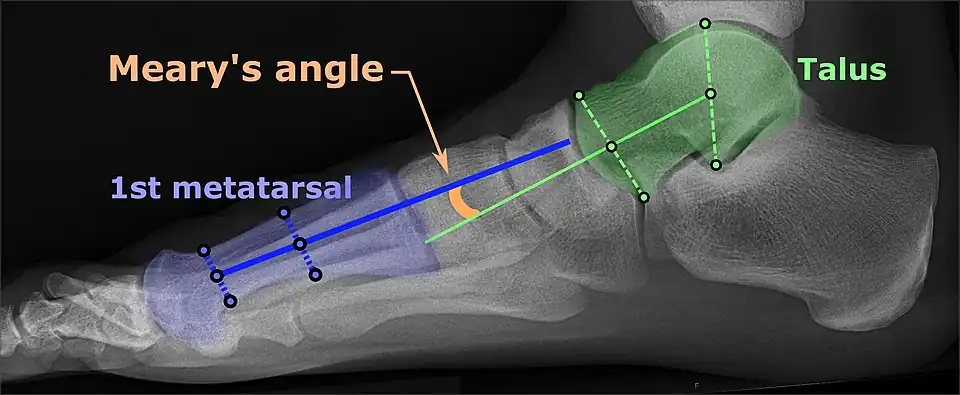

On plain radiography, flat feet can be diagnosed and graded by several measures, the most important in adults being the talonavicular coverage angle, the calcaneal pitch, and the talar-1st metatarsal angle (Meary's angle).[11] The talonavicular coverage angle is abnormally laterally rotated in flat feet.[11] It is normally up to 7 degrees laterally rotated, so a greater rotation indicates flat feet.[11] Radiographies generally need to be taken on weightbearing feet in order to detect misalignment.[12]